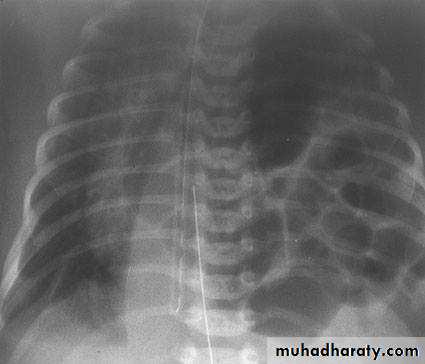

Diaphragmatic hernia